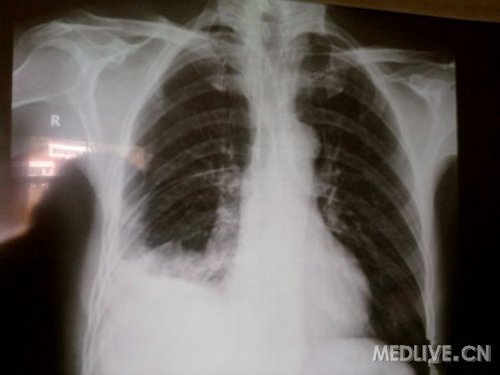

59岁患者,外伤致使右侧血气胸八天入院,肺组织压缩10%,经过胸腔闭式引流术后引流产暗红色淤血约2000毫升,后再次复查胸片仍有血液,胸腔闭式引流未再引出血液,拔出引流管,经彩超定位拟行穿刺抽液,彩超报告有约3.2厘米液体,但已经凝固,无法抽出。

现将片子传上,请各位帮忙看看是不是需要开胸取血块?

事后回想是否引流后暗红色血性液体较多,结合第一张x片胸腔积液量中等以上,是否亚急诊胸腔镜探查更好。现在已几近凝固是否考虑先用尿激酶,,